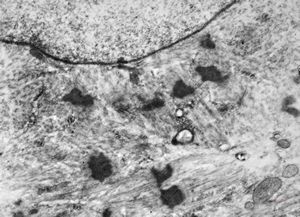

F,25y. | myopathy - atrophic and regenerating muscle cells

M,2y. | myopathy - regenerating muscle cell